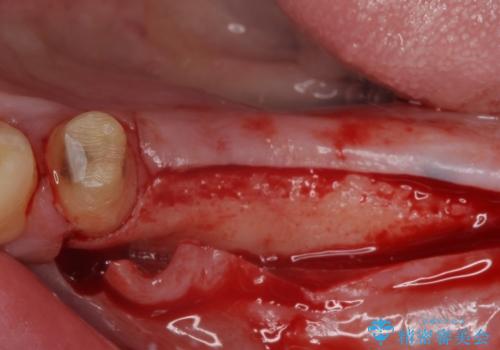

- 地元ではなかなかインプラント治療を行ってくださる医院がないとのことで、転勤で東京にいる期間に治療を行いたいとのことで来院された患者様です。

上顎は左右ともに骨が少ない状態であり、特殊なドリルを用いた歯槽骨の拡大や自家骨挙上などを行いながらインプラントを埋入していくこととしました。